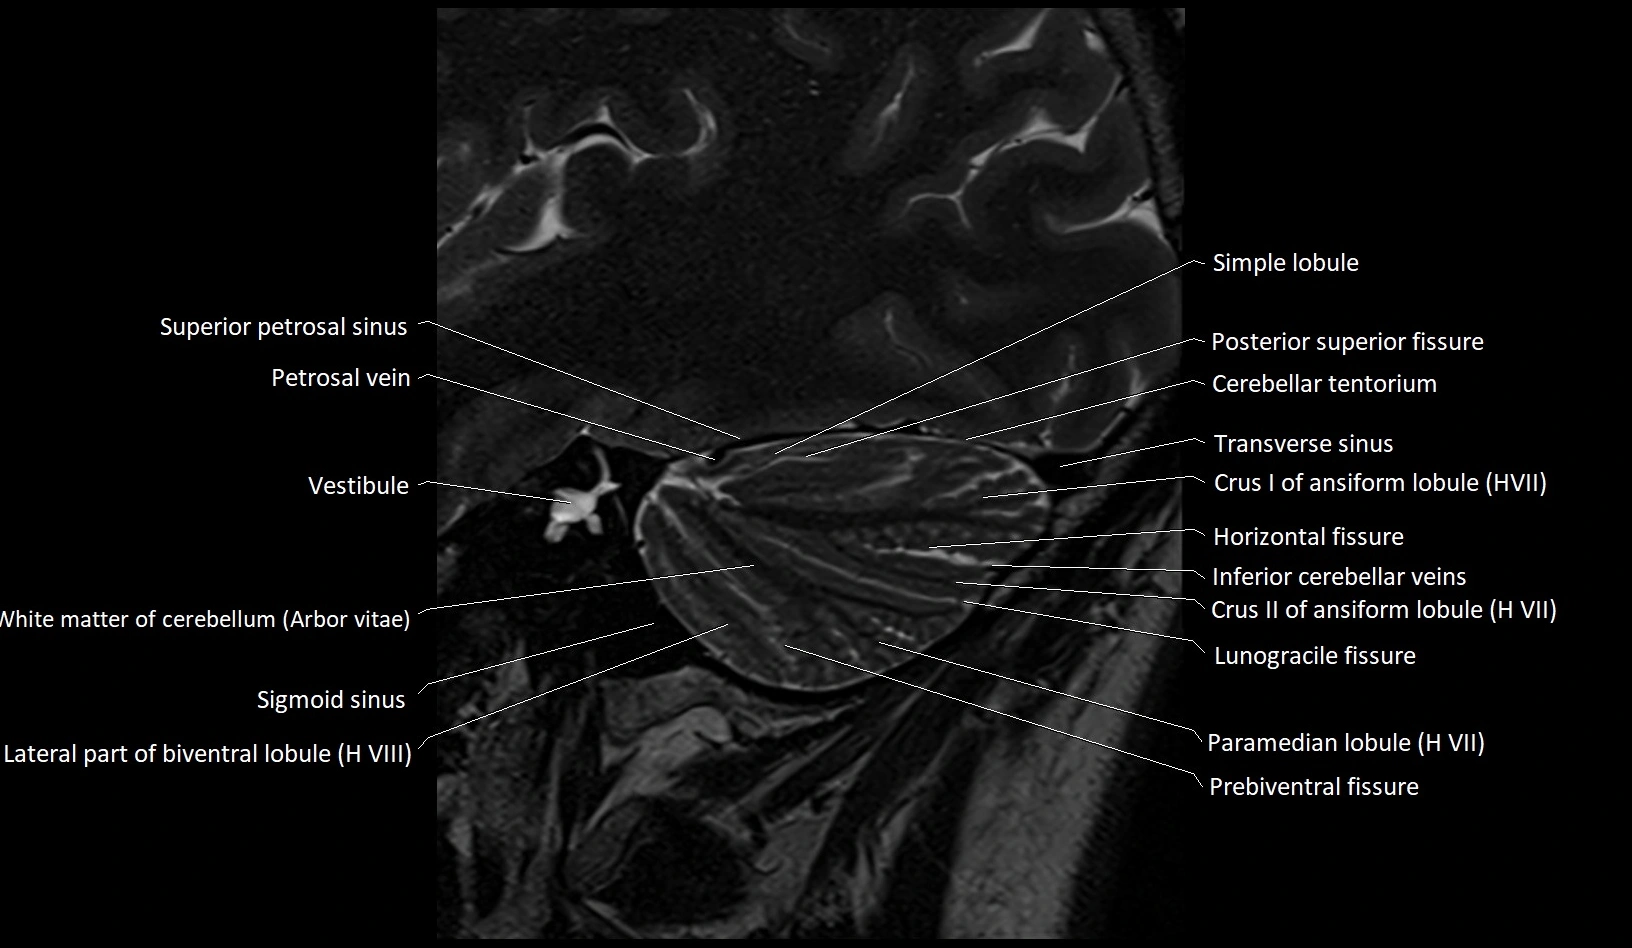

- Arbor Vitae (Cerebellar White Matter)

- Horizontal fissure (cerebellum)

- Inferior cerebellar veins

- Lateral part of biventeral lobule

- Lunogracle fissure

- Occipital sinus

- Paramedian lobule

- Paramedian lobule (HVII) of cerebellum

- Petrosal vein

- Posterior superior fissure

- Prebiventral fissure

- Sigmoid sinus

- Simple lobule

- Simple lobule (HVI) of cerebellum

- Superior petrosal sinus

- Transverse sinus

- Vestibule

- White matter of cerebellum (Arbor vitae)